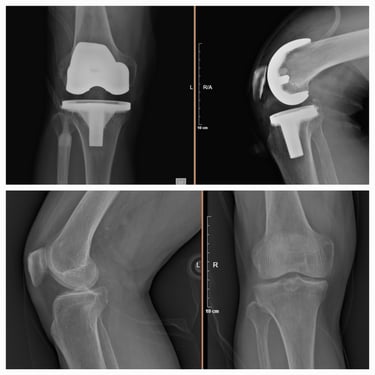

Artroplastia de rodilla (prótesis total/parcial).

Cirugía de revisión de cadera y rodilla.

Manejo de secuelas y complicaciones de prótesis de cadera y rodilla.